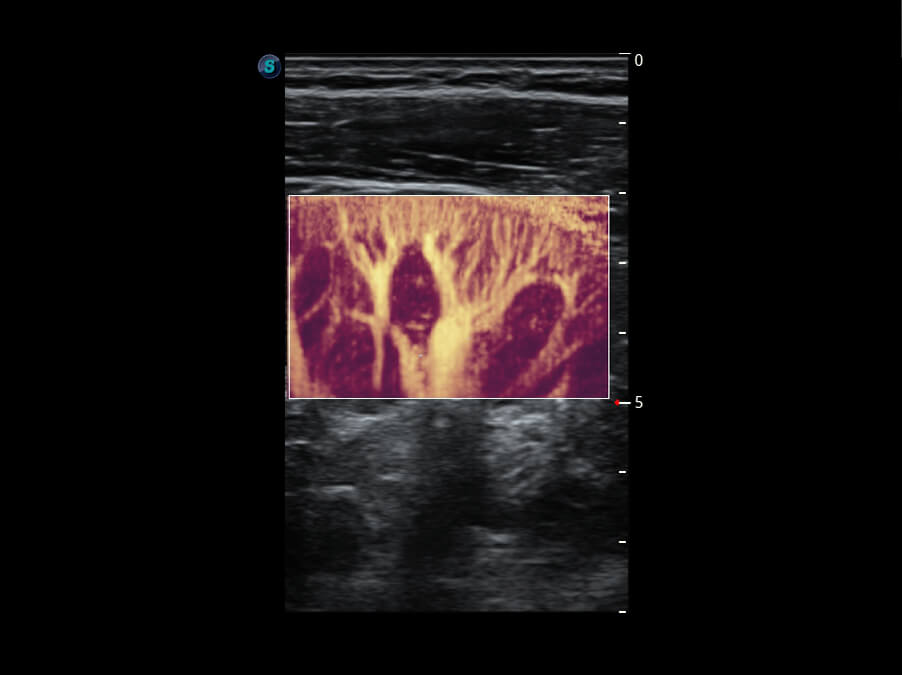

成像功能

S60探头工艺,从前端信号处理每一个环节采集无损声学数据,真实还原组织原貌,再现解剖细节。